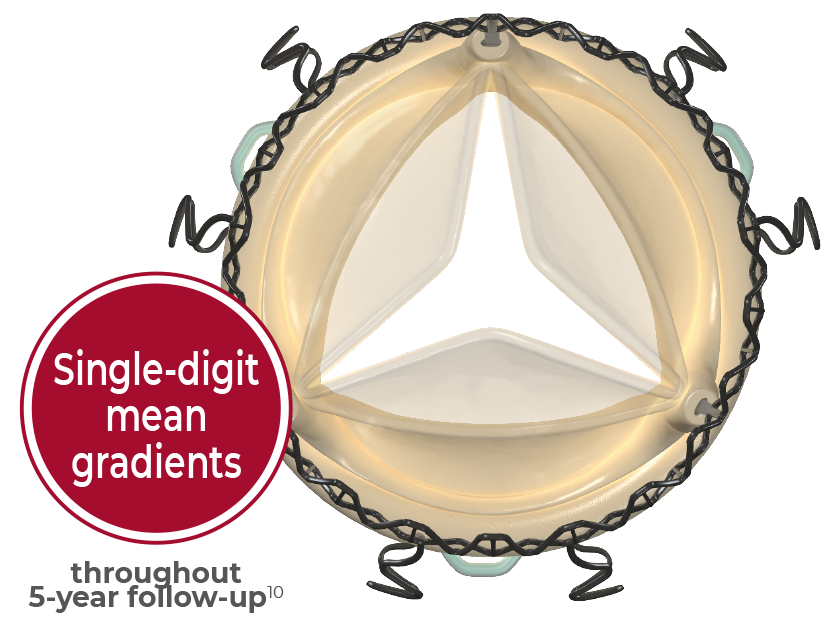

Designed for durability

Superlastic stent

- Self-expands in place (no need to knot the sutures), ensuring optimal valve sealing.2

- Reduces the stress transferred to the leaflets.4

- CarbofilmTM coated to reduce inflammatory reaction and favor a gentle endothelialization.5,6,7

Double sheet design

An outer sheet acts as a cushion that minimizes stress transferred to the leaflets.

Fully atraumatic collapsing

The collapsing procedure does not affect the leaflets preventing any possible damage to the tissue.8

Perceval Plus is based on the trusted Perceval Platform, that has shown a linearized rate of SVD of 0.54% per patient-years with a maximum follow-up of 13 years.9

Designed for excellent hemodynamics

Perceval Plus boasts a distinctive design built around a superelastic stent that self-expands in place (no need to knot the sutures), ensuring optimal valve sealing.2

The Nitinol stent allows Perceval Plus to follow the physiological movement of the aortic root during the cardiac cycle, mimicking the native valve.10,11